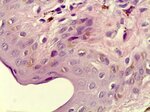

Гистопатологическое заключение:

сложный пигментный невус с тяжелой дисплазией 3 степени.

Фото гистологических срезов:

Displaziia100_2.jpg